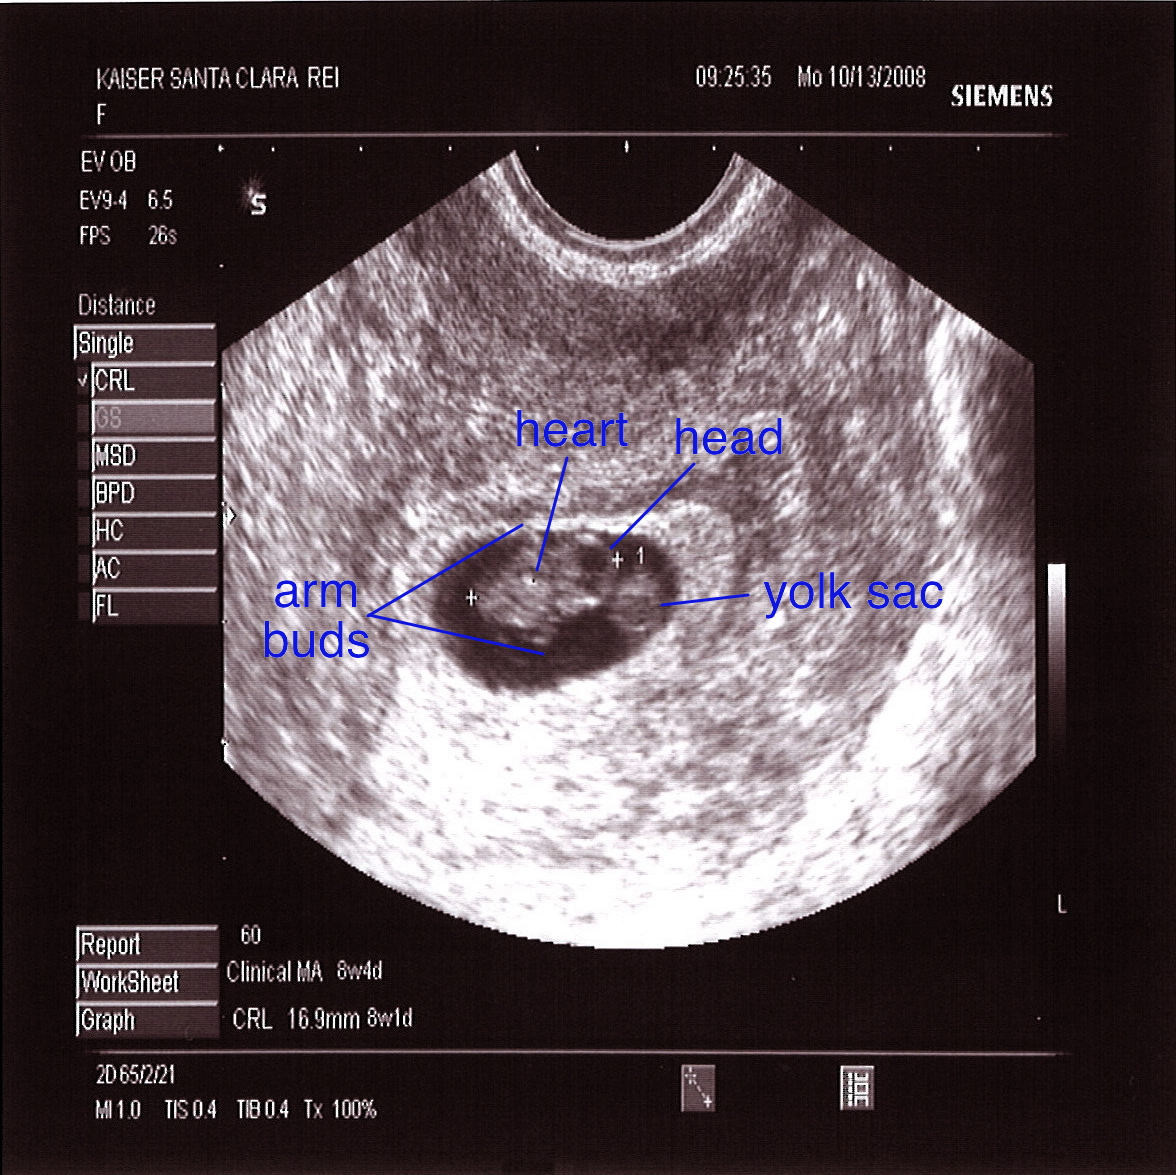

ultrasound at 3 weeks pregnant pictures

Understanding Your Baby’s Development in Week 3

3 Weeks Pregnant – Pregnancy Week-by-Week

The Pregnancy Diaries: I’m 8 weeks pregnant! – Life Education Council

Ultrasound Leadership Academy: Ultrasound in Early Pregnancy — EM Curious